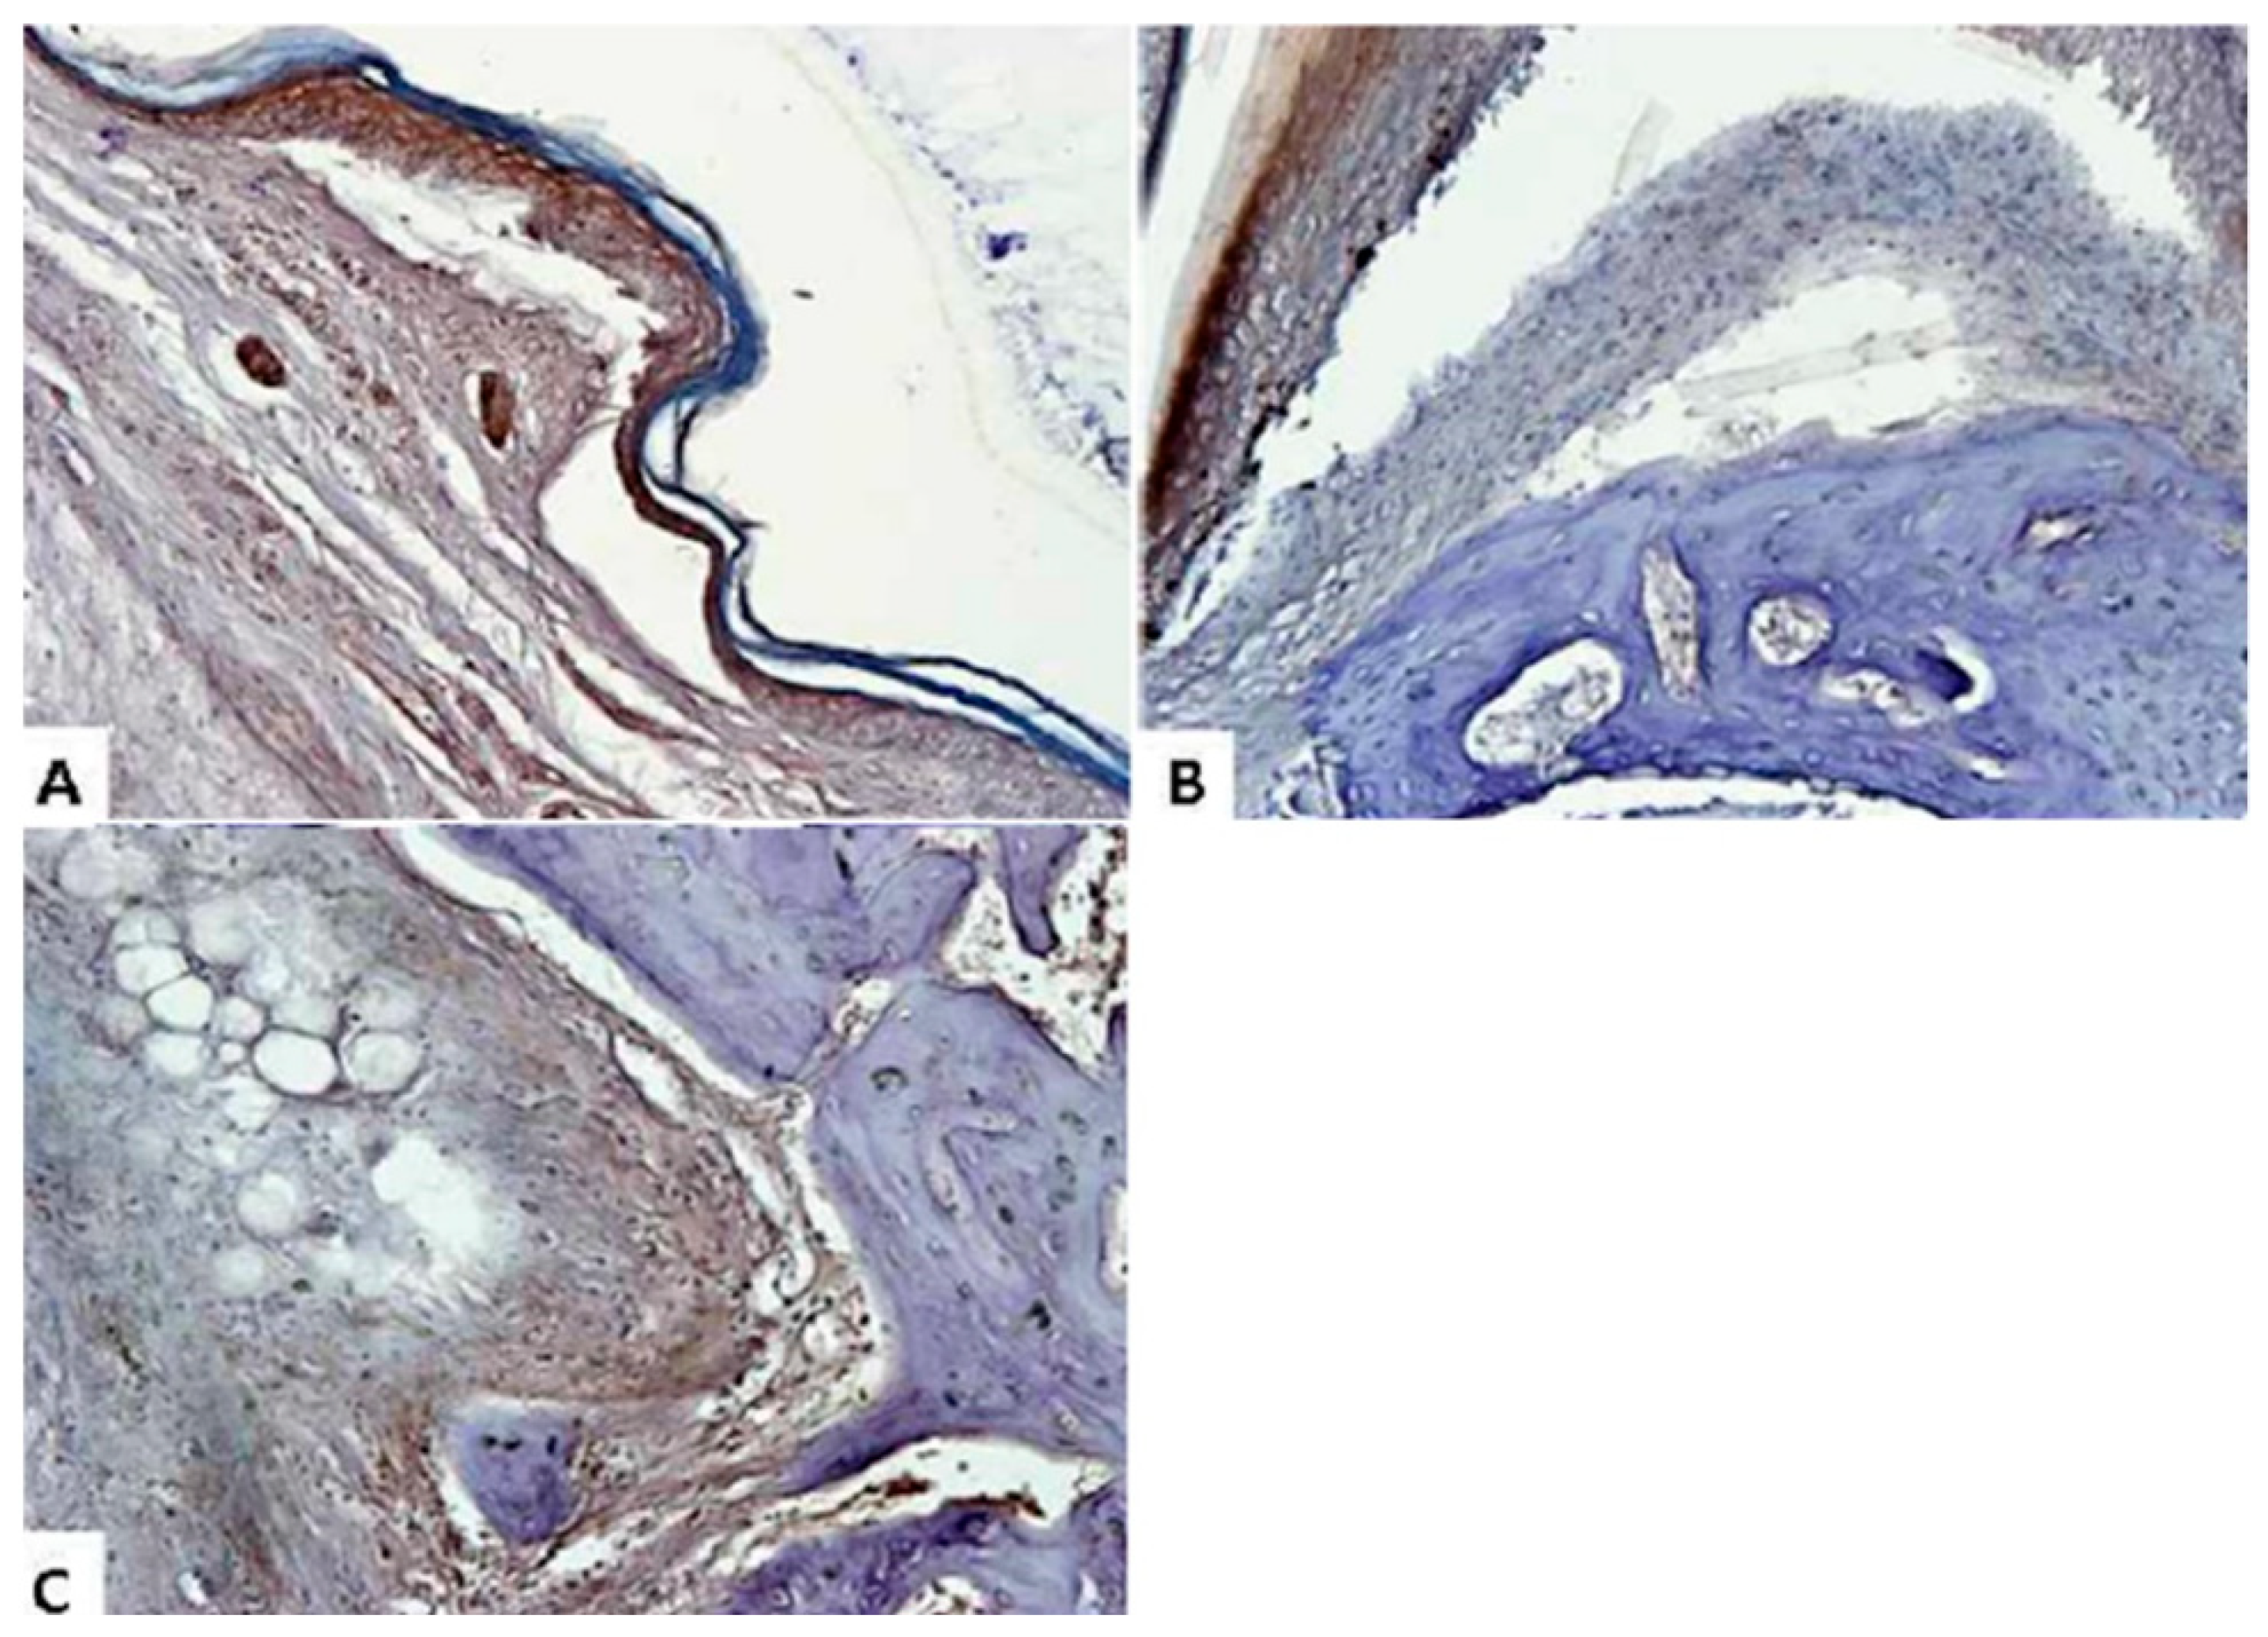

2.4. Sargassum muticum Extract Suppresses Joint Degradation in CIA Mice

2.5. Sargassum muticum Extract Decreases the Expression of Inflammatory Cytokines in CIA Mice

4.4.7. Histological Staining

4.4.8. Immunohistochemical Staining